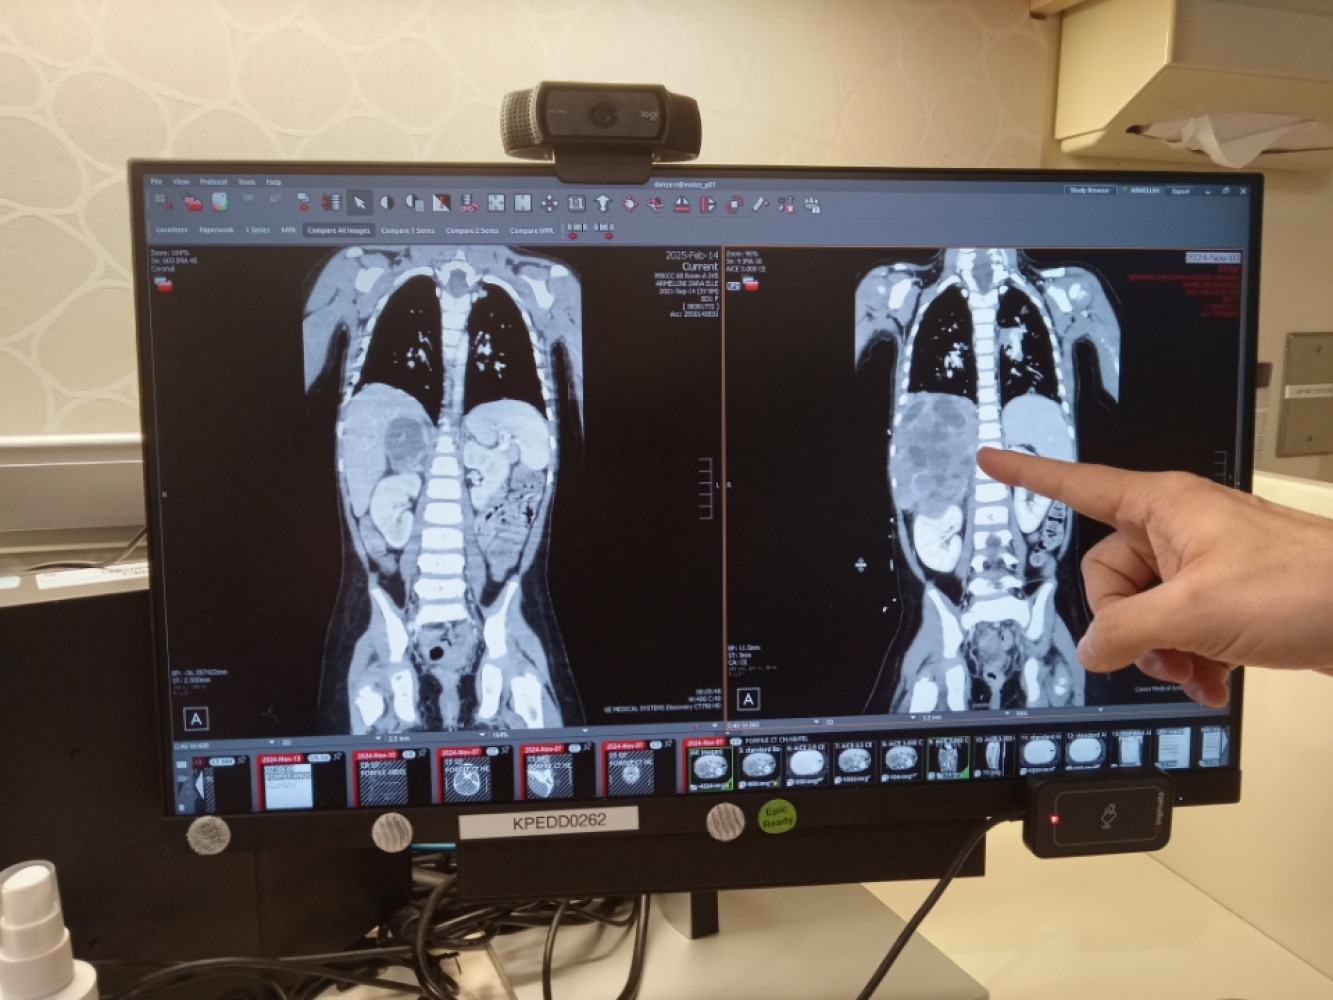

Zara was recently diagnosed with stage 4 metastatic neuroblastoma, a rare and aggressive form of cancer that has spread throughout her body. The rapid progression of her illness has left her parents, Ellyssa and John, facing overwhelming challenges. Ellyssa has been unable to work while staying by Zara’s side, and John has been caring for the girls full time, unable to work as well. Their focus is entirely on supporting Zara, which has made it incredibly difficult to manage the financial burden of medical bills, groceries, and the daily commute to and from the hospital.